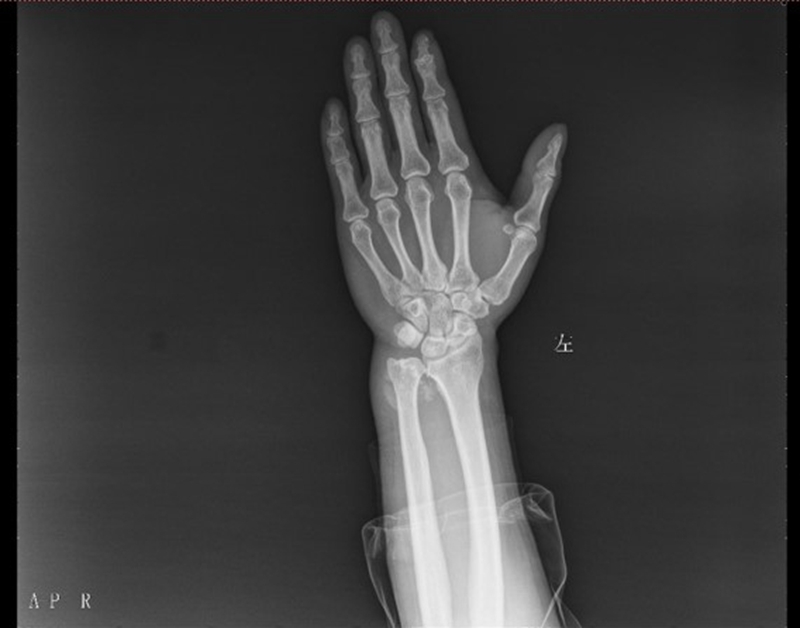

患者周X,男,47岁,发现左腕部包块1年余入院,入院查体:左腕尺侧肿胀明显,可及一质软包块,呈类圆形,可推动,左小指、无名指感觉减退,活动无受限,左手其余指感觉、活动无异常,既往体健,否认高血压、糖尿病病史,无手术史,无药物、食物过敏史

左腕关节正位片提示:左腕尺侧实性占位

左腕关节核磁共振:左腕尺侧软组织占位